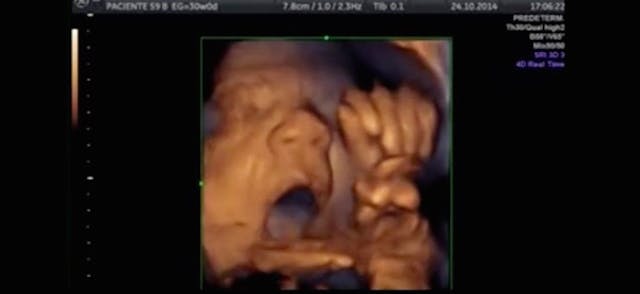

I gather that the really big news, as always, had to do with a commercial advertisement that was broadcast in the course of the game. Evidently, a potato chip manufacurer, or some such profit-driven purveyor of packaged foodstuffs, showed a video image of an unborn baby. This shocked and appalled the folks at NARAL, the big abortion lobby, who promptly accused the company responsible for the ad of “humanizing the fetus.” Since, however, the fetus in the video was, by all accounts, a human fetus, the offspring of human parents, and not a bovine, canine, or feline fetus, it’s less than clear how it is that the potato chip company (or whatever it was) is to blame for the humanization. Surely NARAL’s complaint would be more fairly lodged against God, or nature, or plain old biological reality.

As John Jalsevac of LifeSiteNews says: “Memo to NARAL: that’s what an unborn baby actually looks like.”